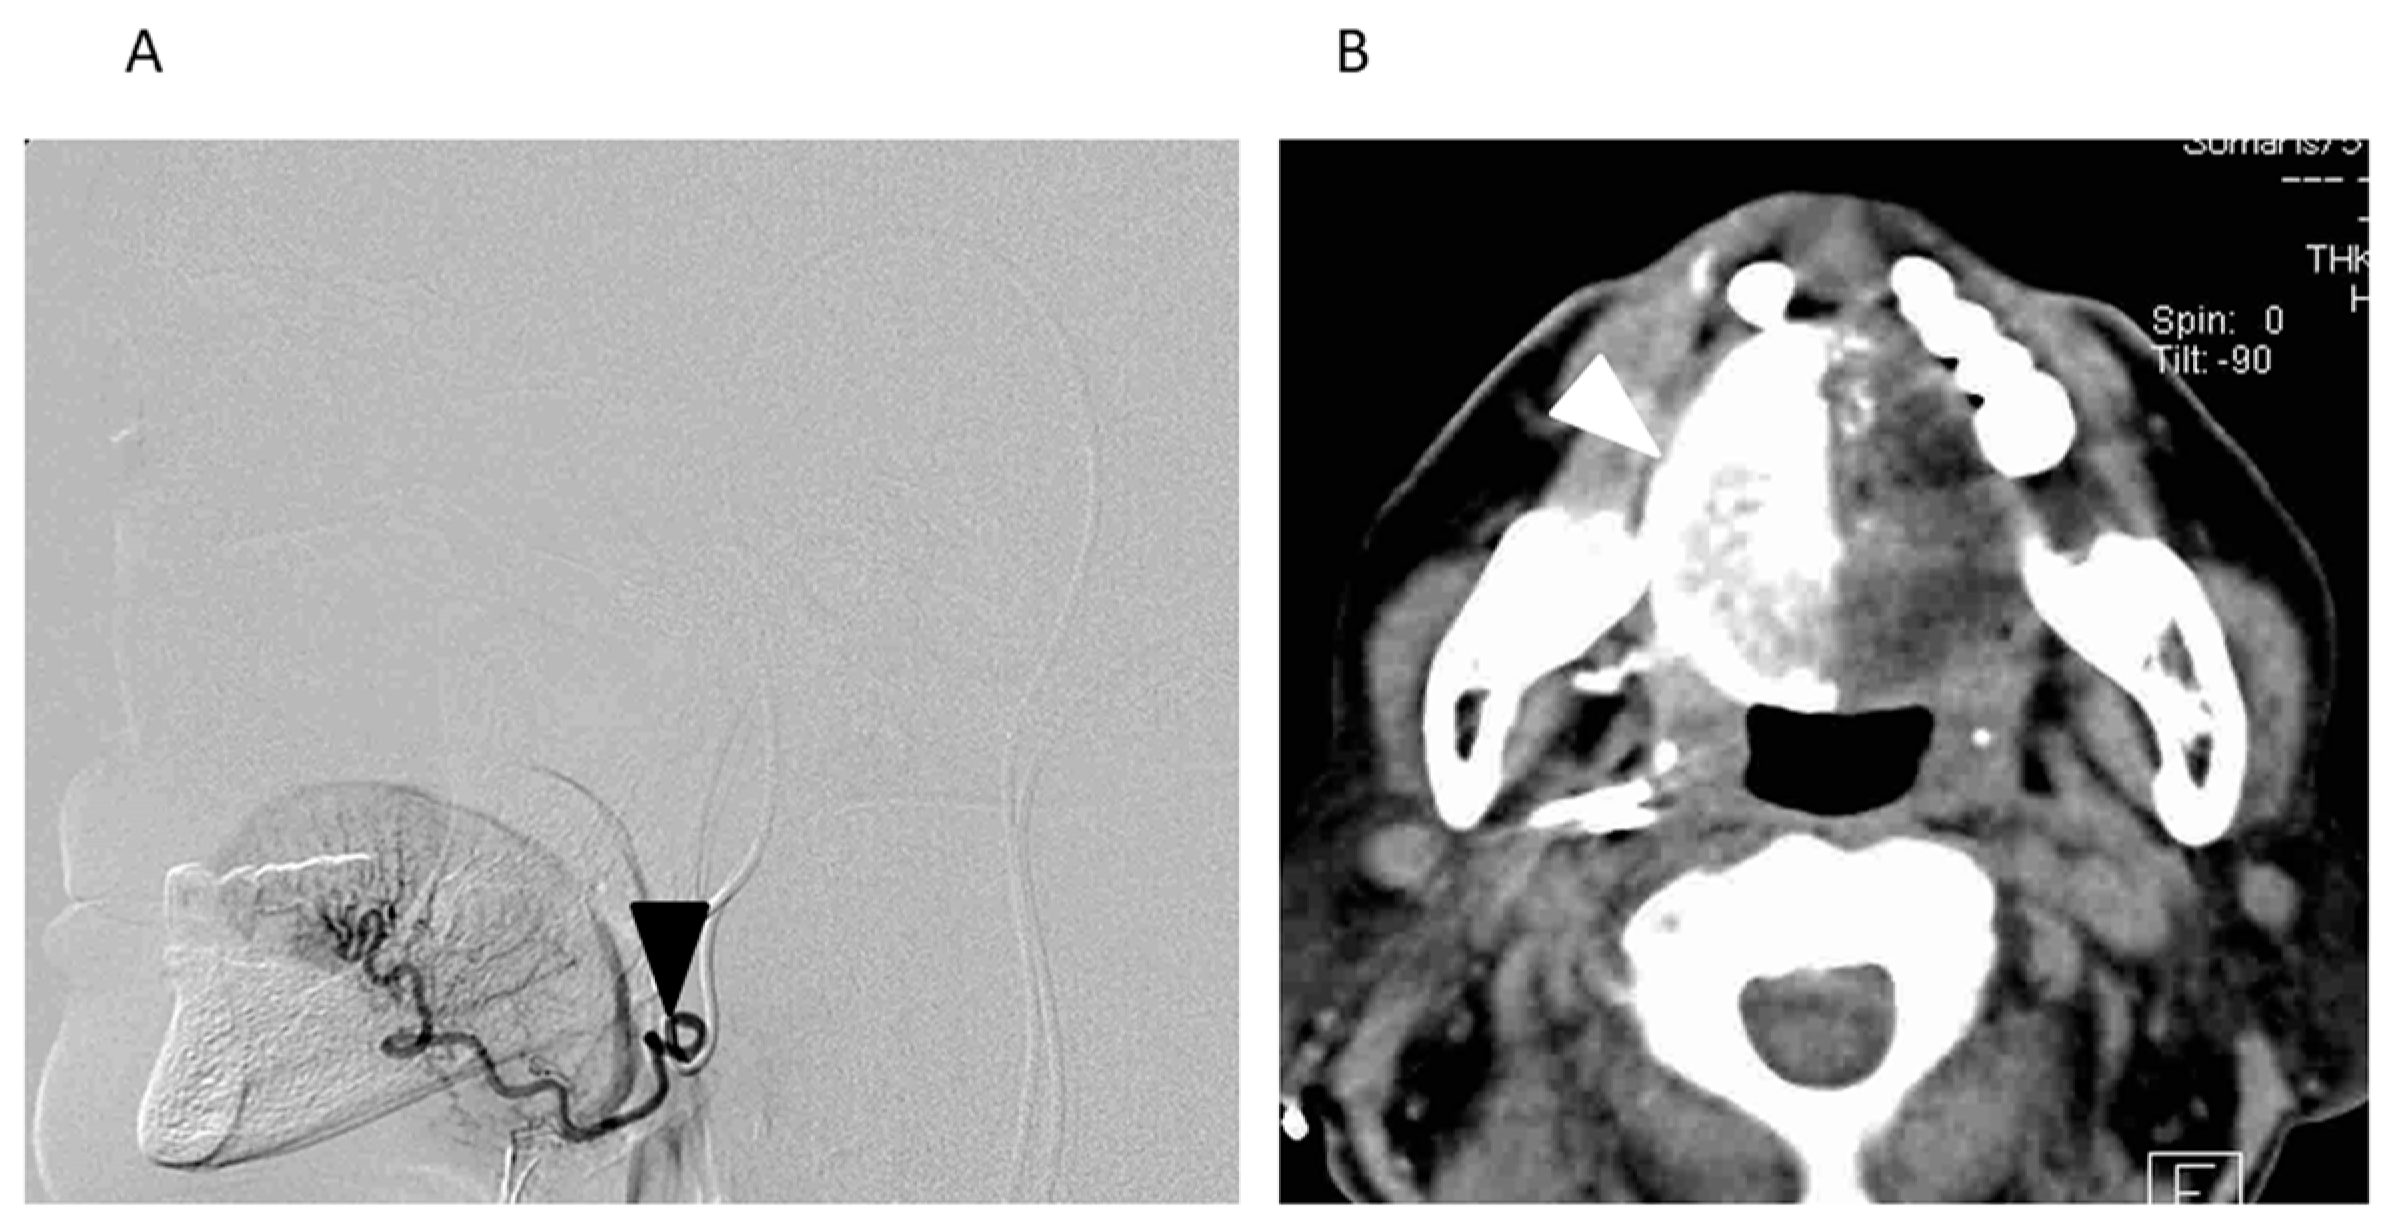

- Mitsudo, K.; Koizumi, T.; Iida, M.; Iwai, T.; Nakashima, H.; Oguri, S.; Kioi, M.; Hirota, M.; Koike, I.; Hata, M.; et al. Retrograde superselective intra-arterial chemotherapy and daily concurrent radiotherapy for stage III and IV oral cancer: Analysis of therapeutic results in 112 cases. Radiother. Oncol. 2014, 111, 306–310. [Google Scholar] [CrossRef] [PubMed]

- Iwai, T.; Fuwa, N.; Hirota, M.; Mitsudo, K.; Tohnai, I. Secure Surgical Method for Catheter Placement via the Occipital Artery to Achieve Retrograde Superselective Intra-Arterial Chemotherapy for Advanced Oral Cancer: Alternative to Approach via the Superficial Temporal Artery. Indian. J. Otolaryngol. Head Neck Surg. 2014, 66, 205–207. [Google Scholar] [CrossRef] [PubMed]

- Fuwa, N.; Kodaira, T.; Furutani, K.; Tachibana, H.; Nakamura, T. A new method of selective intra-arterial infusion therapy via the superficial temporal artery for head and neck cancer. Oral Surg. Oral Med. Oral Pathol. Oral Radiol. Endod. 2008, 105, 783–789. [Google Scholar] [CrossRef] [PubMed]

- Fuwa, N.; Kodaira, T.; Furutani, K.; Tachibana, H.; Nakamura, T.; Nakahara, R.; Tomoda, T.; Inokuchi, H.; Daimon, T. Intra-arterial chemoradiotherapy for locally advanced oral cavity cancer: Analysis of therapeutic results in 134 cases. Br. J. Cancer 2008, 98, 1039–1045. [Google Scholar] [CrossRef] [PubMed]

- Fuwa, N.; Kodaira, T.; Furutani, K.; Tachibana, H.; Nakamura, T.; Nakahara, R.; Tomoda, T.; Inokuti, H.; Daimon, T. Arterial Chemoradiotherapy for Locally Advanced Tongue Cancer: Analysis of Retrospective Study of Therapeutic Results in 88 Patients. Int. J. Radiat. Oncol. Biol. Phys. 2008, 72, 1090–1100. [Google Scholar] [CrossRef] [PubMed]

- Mitsudo, K.; Hayashi, Y.; Minamiyama, S.; Ohhashi, N.; Iida, M.; Iwai, T.; Oguri, S.; Koizumi, T.; Kioi, M.; Hirota, M.; et al. Chemoradiotherapy using retrograde superselective intra-arterial infusion for tongue cancer: Analysis of therapeutic results in 118 cases. Oral Oncol. 2018, 79, 71–77. [Google Scholar] [CrossRef] [PubMed]